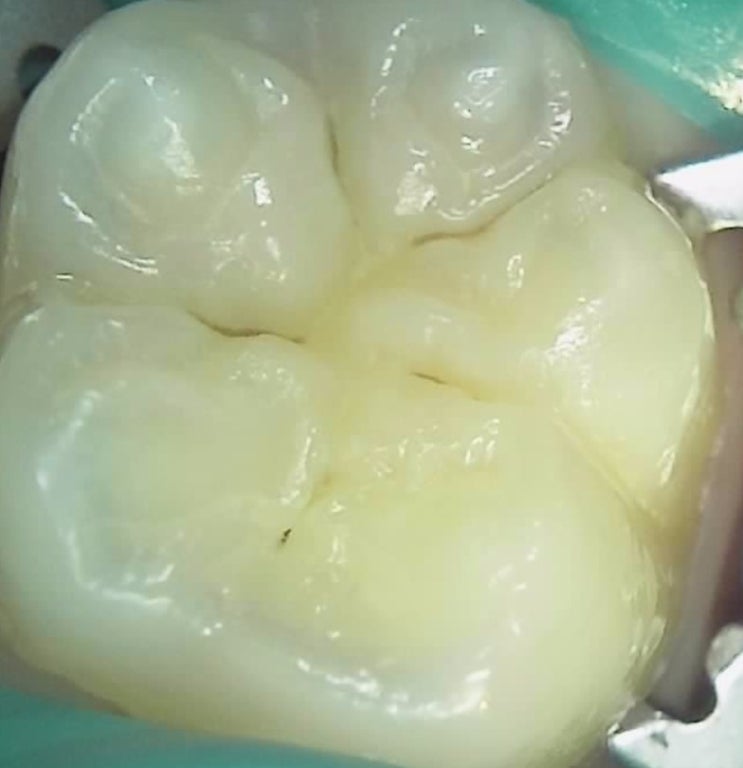

아이들은 영구치 레진치료가 보험이 적용된다는 사실 아시나요? by 대림동 어린이치과 소아치과전문의

안녕하세요 구로 오류동 연세패밀리치과 소아치과전문의 장원장입니다. 이렇게 치아에 충치가 있는경우 치...